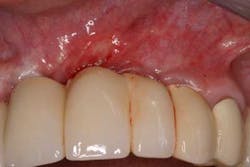

Keratinized tissue around implants can be one method of increasing resistance to bacterial infection. In fact, in a recent review by Greenstein and Cavallaro, the authors listed several indications that necessitated keratinized tissue presence around dental implants. These included patients with chronic inflammation despite hygiene efforts (Fig. 2), continued recession or attachment loss despite periodontal intervention, sites with soreness upon brushing, a predisposition toward periodontitis or recession, noncompliant patients, and those patients who want to improve esthetics (20).

Fig. 2: Persistent inflammation around a dental implant restoration with deficient keratinized tissue despite adequate oral hygiene.